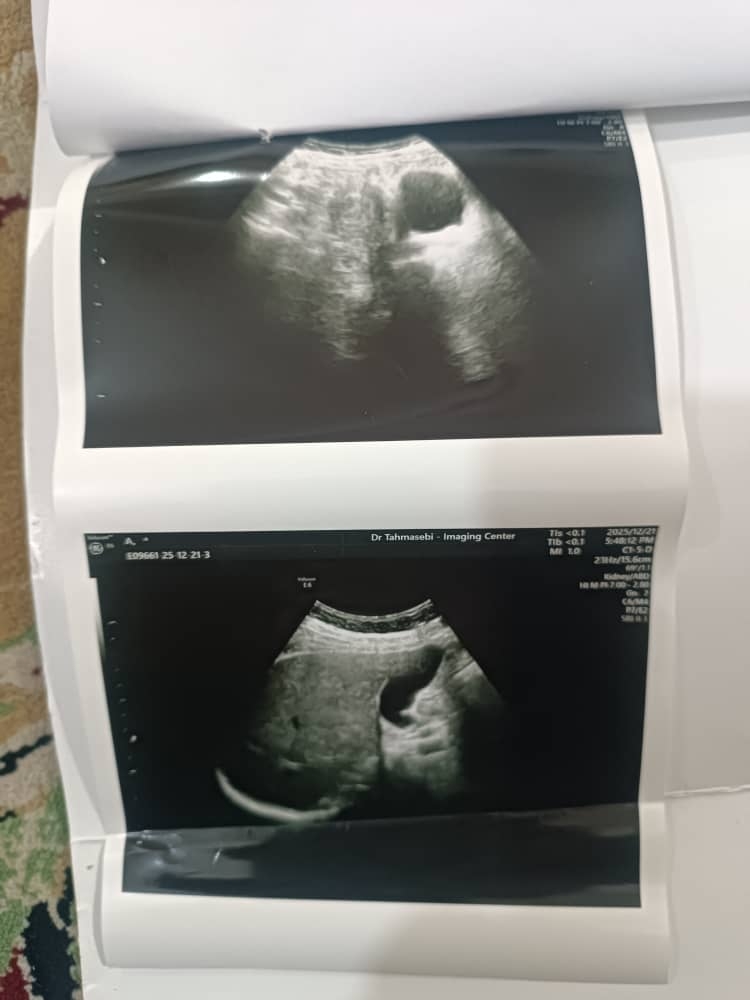

سلام وقت بخیر دکترعزیز خسته نباشید سونو گرافی شکم و لگن مامانم ببینید آیا مشکلی داره ؟

مامانم ی مدتیه ورم معده داشت که پارسال بااندوسکوپی فهمیدیم و بادارو خوب شد ولی یکی دوماه بی اشتهایی داشت دوباره دکتربراش سونوشکم و لگن نوشتن انجام داد تروخدا اگه مشکلی چیزی هست بگین

نه عزیزم گفتم توی پانکراس یا لوزالمعده گفتن احتمالا التهاب هست که دو نوع داره مزمن یا حاد و علل مختلف داره از جمله سنگ کیسه صفرا و الی آخر بسته به اینکه علت کدومه ممکنه گاها بستری لازم باشه

خب پس فیبروم هیچ کاری لازم نداره هر 6 ماه فقط سونوگرافی بدن ابعاد خیلی سریع رشد نداشت بعدش سالیانه سونوگرافی پیگیری بدن❤️

خواهش میکنم عزیزدل من نه اصلا اصلا نگران نباشی، رحم عالی تر از عالیه هیچ مشکلی نداره ❤️🌹😘

فیبروم مثل خال گوشتی هست اغلب خانما دارن تا بزرگ نشه علامت دار نشه کاری بهش نداریم ❤️